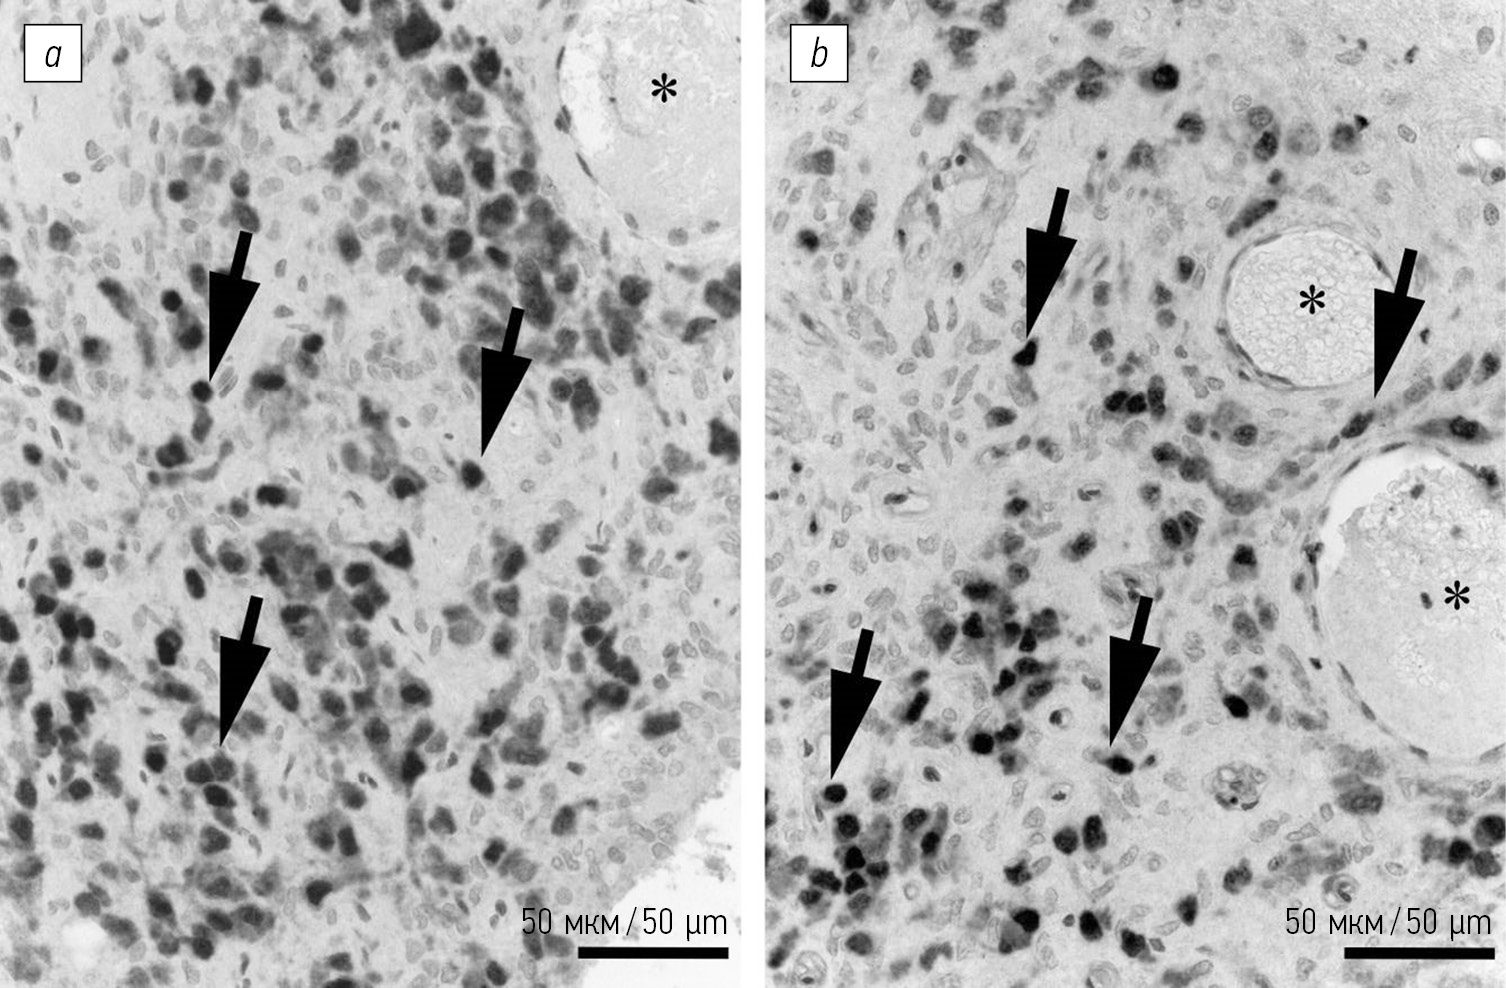

Рис. 1. NeuN в субфорникальном органе крыс: а — Вистар, с — SHR. Иммуногистохимическая реакция на NeuN с подкраской альциановым синим. Микрофотографии субфорникального органа крыс Вистар (b) и SHR (d), преобразованные методом кластеризации по плотности (алгоритм DBSCAN) при ε-окрестности 20 пикселей и минимальной плотности частиц 3. Стрелки указывают на нейроны с интенсивной окраской, головки стрелок — клетки с окраской средней интенсивности. Границы территорий (серый цвет) ограничивают предполагаемые кластеры

Fig. 1. NeuN distribution in the rats SFO: a — Wistar, c — SHR. Immunohistochemical staining of neurons (NeuN) with alcian blue counterstain. Micrographs of the Wistar rat (b) and SHR (d) subfornical organ, transformed using by the density based clustering DBSCAN algorithm. Parameter’s value ε = 20 pixels, minDensity = 3 objects. Arrows indicate intencively stained neurons, arrowheads show neurons with average IHC intensity. Borders (gray) indicate estimated clusters

При изучении гистологических микропрепаратов СФО спонтанно-гипертензивных крыс было отмечено визуальное сокращение популяции нейронов. Нейроны в паренхиме СФО у крыс SHR располагаются неравномерно и разделены глиальными элементами таким образом, что на срезах можно выявить обособленные скопления NeuN-позитивных клеток. Неравномерная интенсивность иммуногистохимической реакции в пределах органа и пониженная ее интенсивность по сравнению с другими наблюдаемыми на срезе областями головного мозга также отмечена у крыс SHR. В каудальной области, как и у крыс Вистар, плотность нейронов визуально значительно снижена. Все выявляемые NeuN-клетки СФО в этой области имели окраску слабой интенсивности. Скопления NeuN-содержащих клеток чаще всего отмечали в центральной части органа, вблизи крупных кровеносных сосудов, а также по периферии СФО — в субэпендимной зоне и на границе с прилежащим белым веществом (рис. 2, b). Оценка распределения NeuN-содержащих клеток с использованием плагина SSIDC Cluster Indicator подтвердила как наличие кластеров в пределах СФО, так и их расположение в основном в центральной и вентральной частях СФО (рис. 1, c, d). Между кластерами часто располагались пустоты, которые при исследовании препаратов при большом увеличении идентифицировали как скопления глиальных клеток.

Рис. 2. Особенности распределения NeuN в субфорникальном органе крыс при развитии артериальной гипертензии. Иммуногистохимическая реакция на NeuN с подкраской гематоксилином, крыса Вистар (a), с подкраской альциановым синим, крыса SHR (b). Стрелки указывают на NeuN-содержащие клетки, звездочки — кровеносные сосуды

Fig. 2. Hypertension-induced NeuN distribution in subfornical organ. NeuN immunohistochemistry with hematoxylin counterstain, Wistar rat (a), with alcian blue counterstain, SHR (b). Arrows indicate NeuN-immunopositive cells, arrows — blood vessels